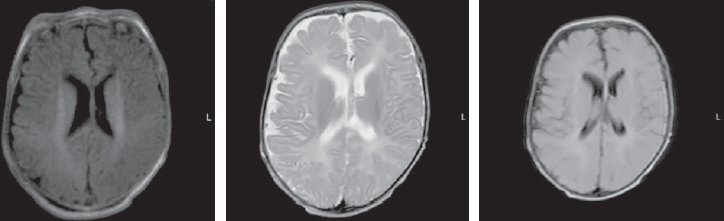

The MRI, performed at seven months of child’s age, revealed a moderate increase in the severity of atrophic changes. Bilateral cystic encephalomalacia of the cerebral hemispheres as well as atrophic hydrocephalus with dilatation of the external and internal cerebrospinal fluid spaces occured. Bilateral chronic subdural hematomas (hygromas) progressed (Fig. 4).

Fig. 4. Magnetic resonance imaging of a patient at the age of 7 months. Axial sections, T1 VI, T2 VI, Flair. There is a bilateral cystic encephalomalacia of the large hemispheres of the brain, atrophic expansion of the external and internal liquor spaces – a moderate increase in the severity of changes. Bilateral chronic subdural hematomas (hygromas) – a moderate increase in fluid volume

Рис. 4. Магнитно-резонансная томограмма пациента в возрасте 7 мес. Аксиальные срезы, Т1ВИ, Т2 ВИ, Flair. Отмечается билатеральная кистозная энцефаломаляция больших полушарий головного мозга, атрофическое расширение наружных и внутренних ликворных пространства — умеренное нарастание степени выраженности изменений. Двусторонние хронические субдуральные гематомы (гигромы) — умеренное увеличение объема жидкости